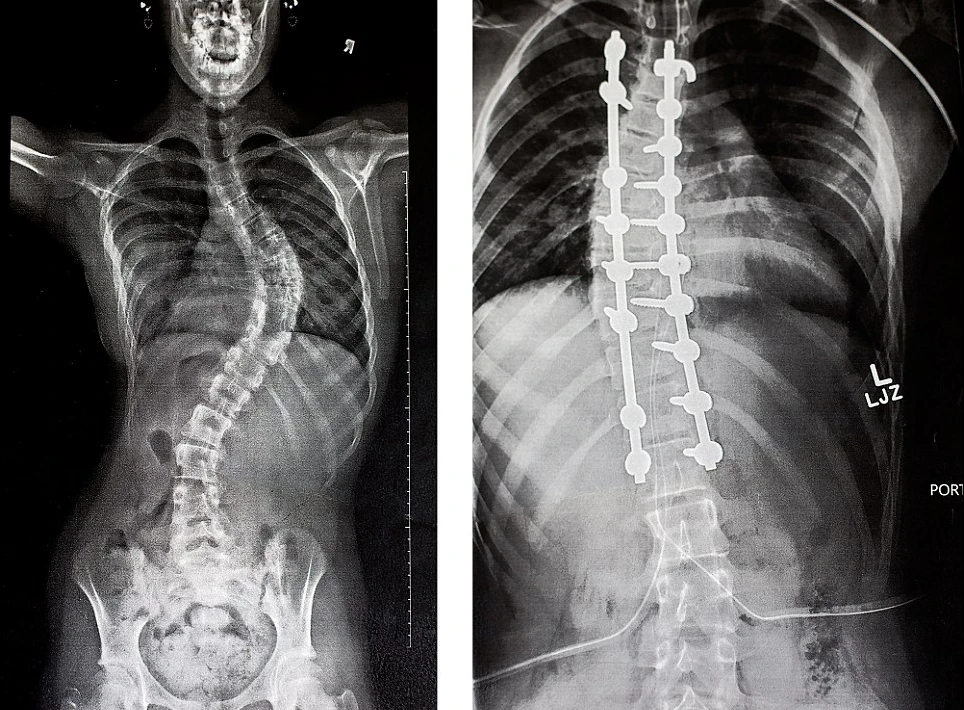

Cột sống của Hannah trước và sau khi phẫu thuật chỉnh hình.

Để thực hiện ca phẫu thuật chỉnh xương sống này, các bác sĩ sẽ phải cố định xương sống của Hannah với các thanh titan, cô bé sẽ phải trải qua thời gian hồi phục 2 tháng cực kỳ đau đớn.